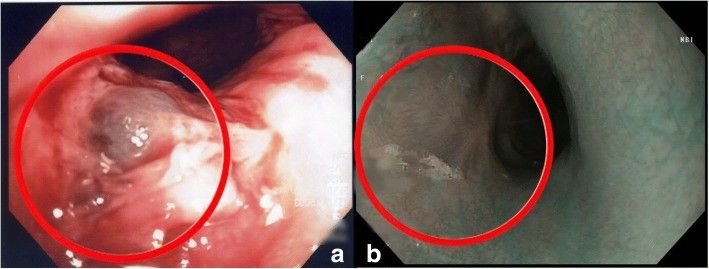

Зонд был удален, установлен баллонный дилататор диаметром 20 мм (CRE PRO, Boston Scientific) — это позволило выполнить аортографию, которая показала экстравазацию контраста, подтверждая подозрение на повреждение аорты несколько выше диафрагмы (рис. 3).

Рисунок 3 [1].

После установки стента в аорту (Advanta™ V12; Atrium Medical Corporation, США; рис. 4) кровотечение было остановлено, достигнута стабильность гемодинамики. Дополнительно проведен эндоскопический гемостаз (Hemospray®; Cook Medical, Ireland). При дальнейших обследованиях рецидива кровотечения не отмечено.

Рисунок 4 [1].